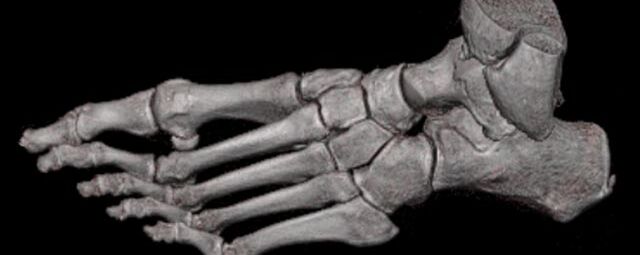

Extremitäten

• bei komplizierten Frakturen z. B. in der Nähe von Gelenken oder im Bereich der Handwurzel und Fußwurzel

Spezielle Software ermöglicht jetzt zum Beispiel:

• verbesserte Bildqualität bei Patienten mit Implantaten (z. Bsp. Hüftendoprothesen)

• besonders hochauflösende, strahlendosissparende Darstellung aller Skelettstrukturen